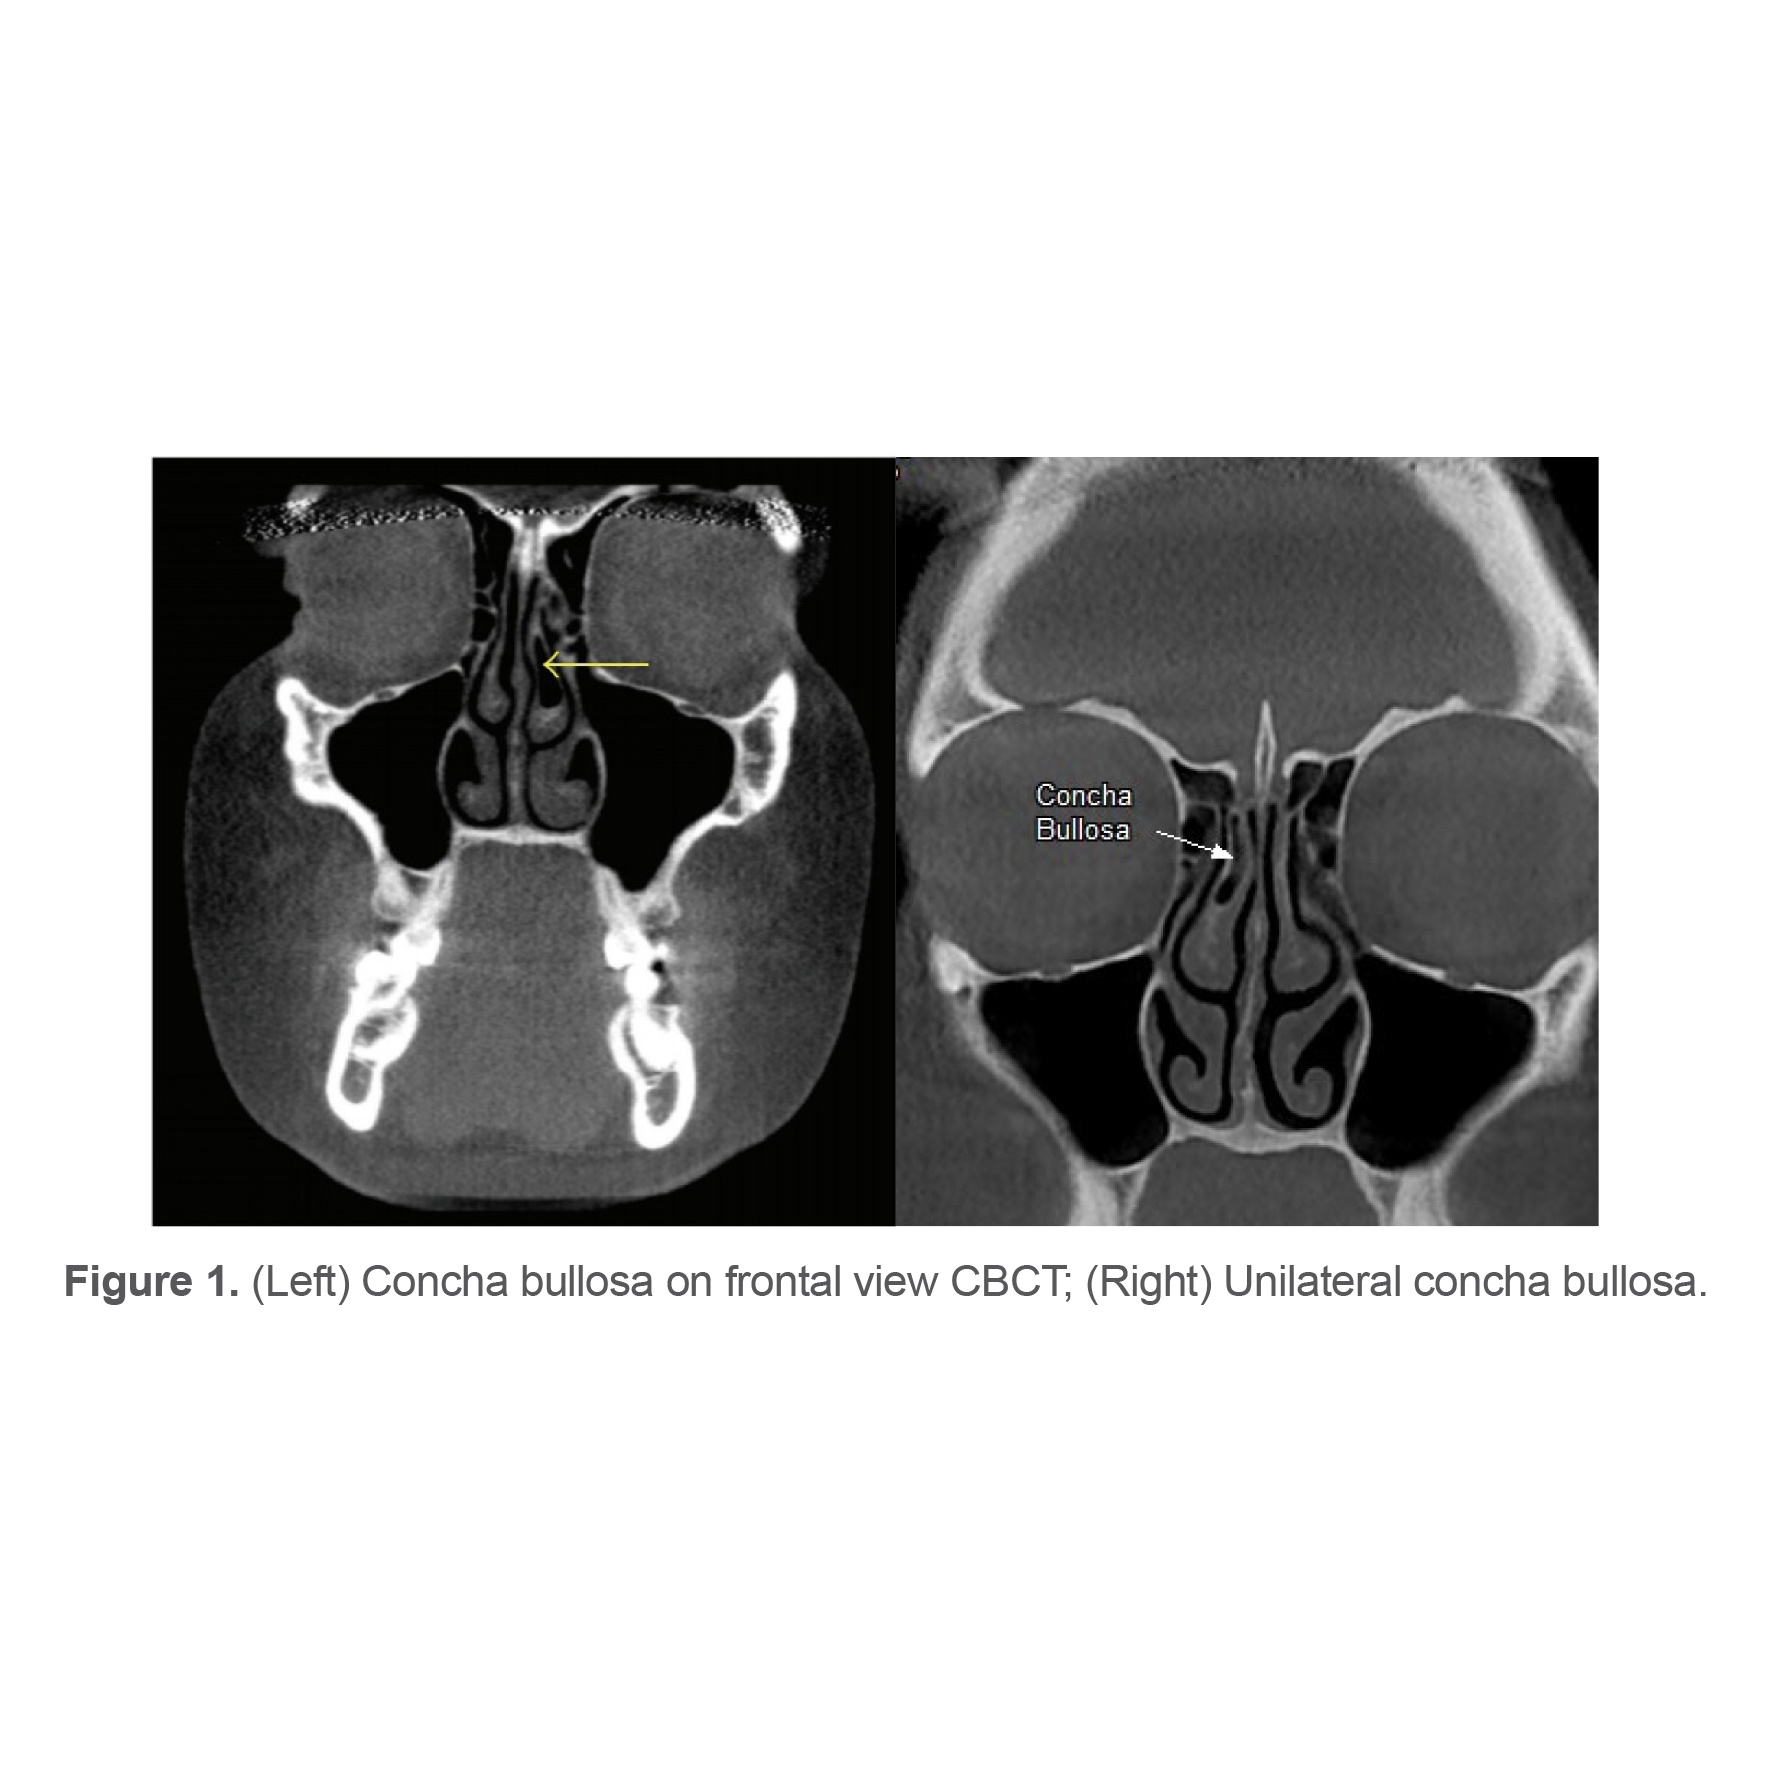

To assess the maxillary sinus MT, the distance between the sinus floor and the uppermost border of the maxillary sinus mucosa was measured on the coronal section by using the digital ruler of the software. Values > 3 mm were considered as presence of maxillary sinus MT (10) (Figure 3). Maxillary sinus MT was categorized as localized, generalized, and Mucous Retention Cyst (MRC) (Figure 4).

Figure 3. Unilateral (Left) and bilateral (Right) maxillary sinus mucosal thickening.